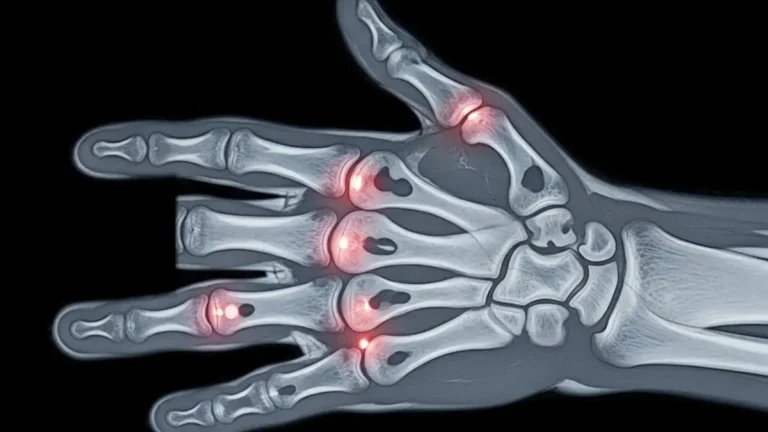

Fratura de boxer é o nome dado à quebra do colo do 5º metacarpo, o osso que liga o dedo mínimo ao punho. Ela costuma acontecer depois de um soco em superfície rígida, mas também pode surgir após quedas, pancadas…